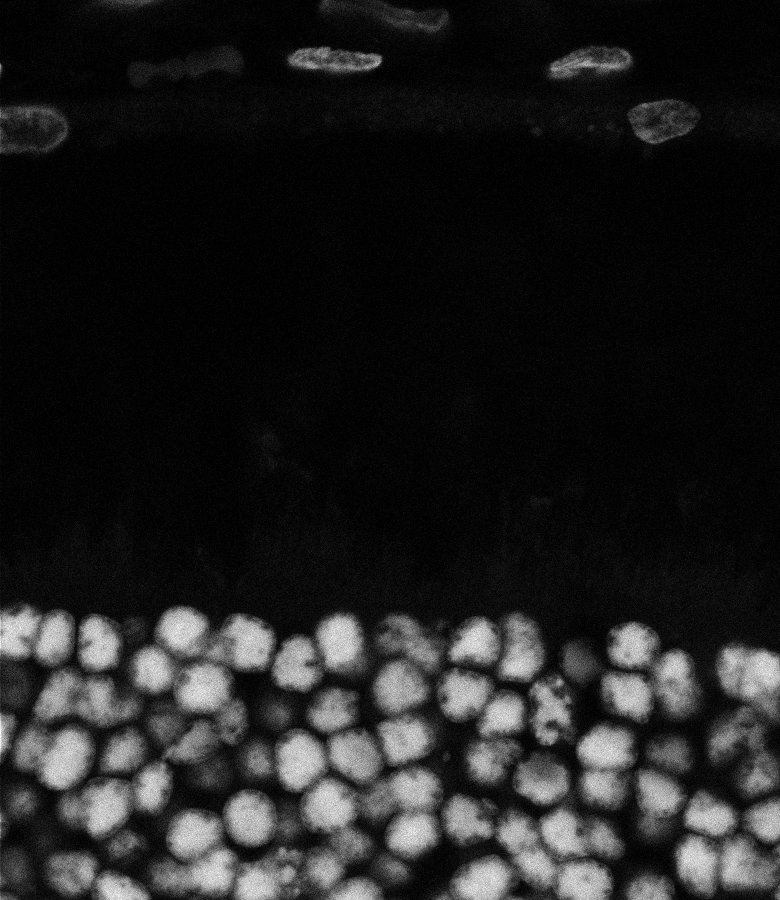

Unhealthy Retina

Nuclei